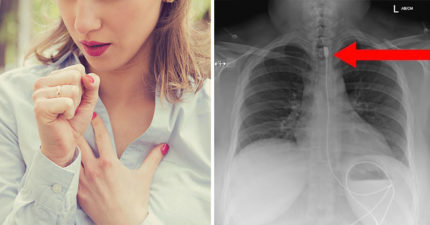

呼吸困難!X光驚見「1公尺iPhone充電線」卡體內 她親吐恐怖真相